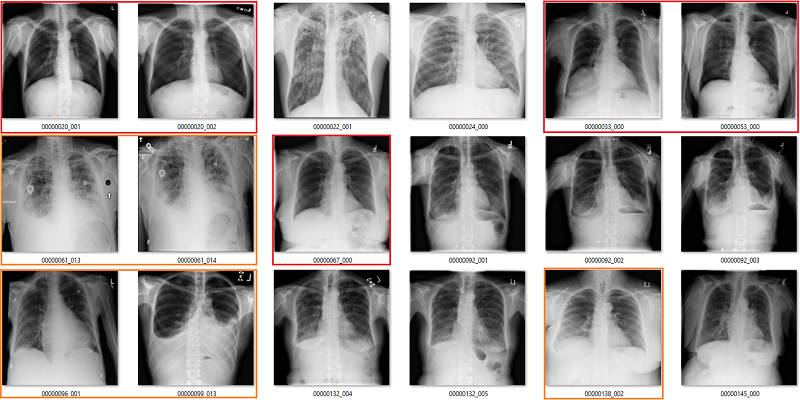

这部分要说该数据集中基于标签的图像。它们是随机选取包含 18 张图像的序列集,并非精挑细选。

我尽量保持谨慎,当一个案例模棱两可的时候,我选择标出标签类别。在所有图像中,红色 = 明显错误的标签;橙色 = 怀疑态度,我没有指出这个问题,但是不能排除这种怀疑。(出于临床诊断的习惯 :p)

心脏扩大(Cardiomegaly)

渗出(Effusion)

在该案例中,蓝色的标签表示它们存在显著性的肺部疾病。

渗出(effusion)表示在肺部周围空间有积液。造成该病变的原因非常多,但主要原因分为由胸膜和肺部疾病引起的积液。

我并不清楚什么确定或代表了显著性肺部疾病中有积液存在。在很多情况下,甚至直观地识别这些积液都是不可能的,只不过我们知道积液会存在,所以我们也就这样描述它了。上图最后三个肺部影像就是一个非常好的例子,在我看来,这些病例的主要病理还是固结(consolidation)。

我可以看到识别较小和分离的胸腔积液的价值。上图中约有 6 张影像是这样的情况,包括第一张和第三张。没有肺部疾病来表明积液的成因,这令标签「积液」越发突兀。

我还可以看到识别较大积液的好处,它们可能需要我们的介入进行治疗,如使用器械将它们排出。第 10 张图就正好是这样的案例。所以其实我并不太了解标签的含义,因为不是基于临床实践的指导思想并不是很有用。